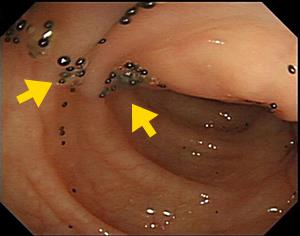

虚血性大腸炎:特徴ある帯状の潰瘍が2条見られます(上)。

接近像:白い部が潰瘍で、周囲にむくみを伴っております(下)。